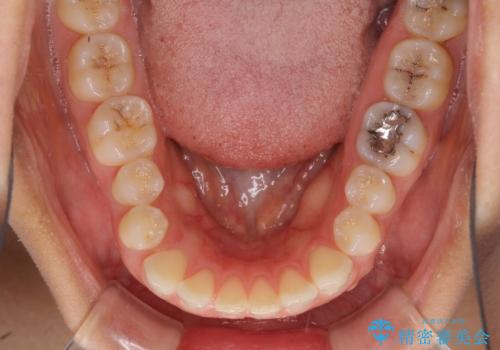

受け口傾向の前歯 すきっ歯の改善

- 前歯の隙間と口元の突出感を気にして来院された患者様です。

嚥下時に舌を突出させる癖があり、成長期に下顎が有意に成長し、歯と歯の間に隙間ができてしまいました。

舌の癖を改善し、インビザラインにて治療を行うこととしました。

舌癖を改善したことで、隙間や突出感を改善することができました。

隙間は後戻りしやすいため、舌側を細いワイヤーで固定することとしました。